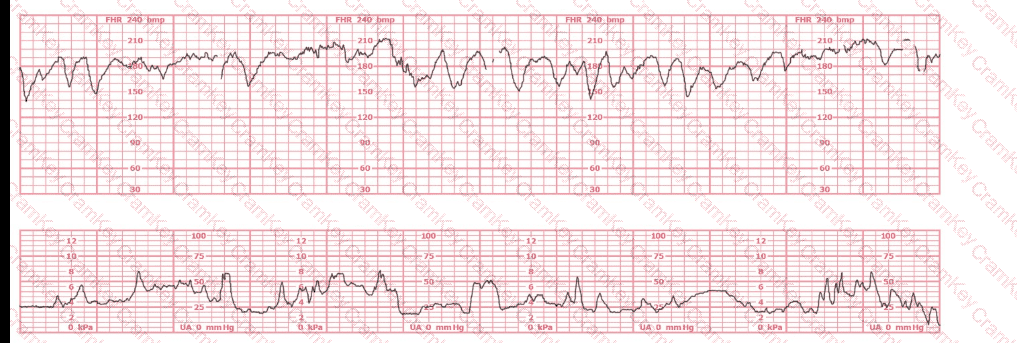

A fetus displays a baseline heart rate of 125 beats per minute with moderate variability. During a contraction, the baseline rate drops abruptly to 80 beats per minute with gradual return to baseline over 90 seconds. This is classified as:

A 30-year-old woman (G2P0) is experiencing preterm labor at 26-weeks gestation. She is receiving magnesium sulfate for neuroprotection. Her external fetal monitoring tracing over the past 30 minutes is shown. The next step would be to:

What is the appropriate interpretation of this tracing?